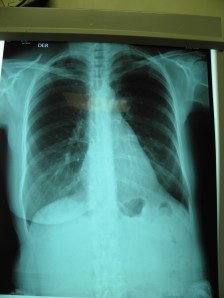

Imaging:

CT scan – showing a large left-sided lung upper lobe mass with chest wall invasion and rib involvement at the level just beneath the scapula.

Chest wall resection  chest mass